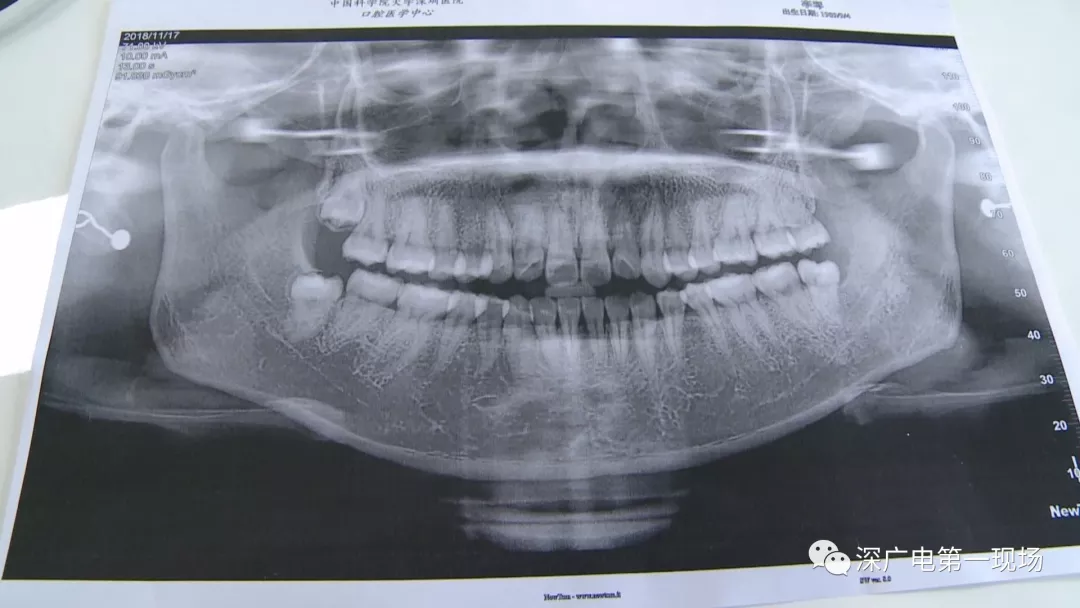

復雜牙拔出程序較復雜

針對李女士的情況,醫(yī)生介紹,當時要想拔出李女士的這顆智齒,難度還是很大的,屬于復雜智齒的拔除術。她的風險在于距離神經(jīng)管近,同時這顆牙齒完全埋在牙床最后的位置,直接往外拔,會加大頜骨的風險,因此需要先切開,讓牙齒暴露后,切小再慢慢地拔出。